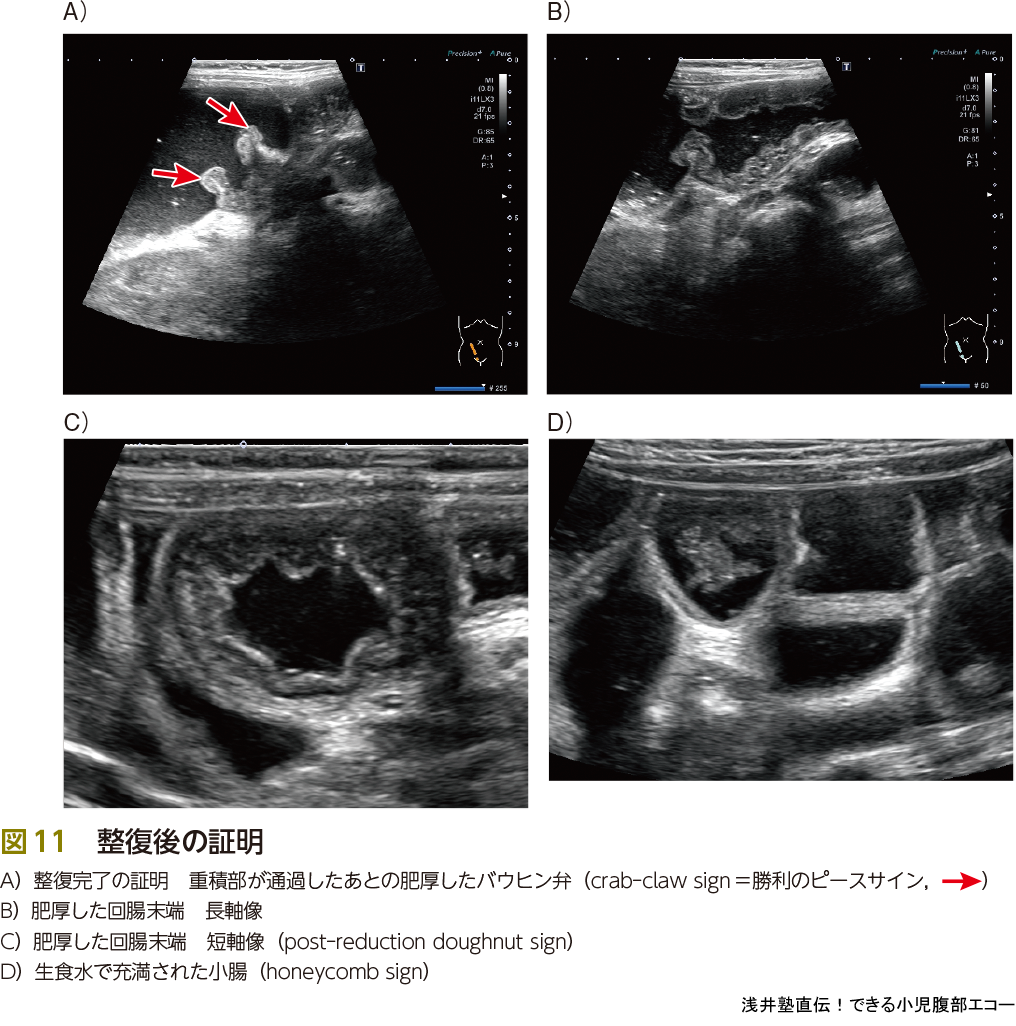

被曝がない,場所を問わない,生理食塩水を注入するために先進部病変の発見が容易になる,穿孔の際に発見が容易…,などいろいろなメリットがあるエコー整復ですが,いまだに浸透していないのが現状です.その理由の1つとして,整復の瞬間を見落とすことが怖いという意見がありました.これは大丈夫です.見落としても整復後のサイン(図11)を確認すれば,その証明になります.重積部が通過した後の肥厚したバウヒン弁は,カニの爪という意味でcrab-claw signとよばれていますが,私は勝手に「勝利のピースサイン」とよんでいます(図11A).また,整復後の肥厚した回腸末端の短軸像をpost-reduction doughnut signとよびます(図11C).生理食塩水で充満した小腸はhoneycomb sign(図11D)とよばれ,重積が解除されてそこまで生理食塩水が到達したことを示します.小腸小腸重積が残存している場合もあるため,最後のhoneycomb signは重要です.また,バウヒン弁を通過する生理食塩水の勢いも口側に小腸小腸重積,つまり通過障害があるかどうかを判断する情報になります.